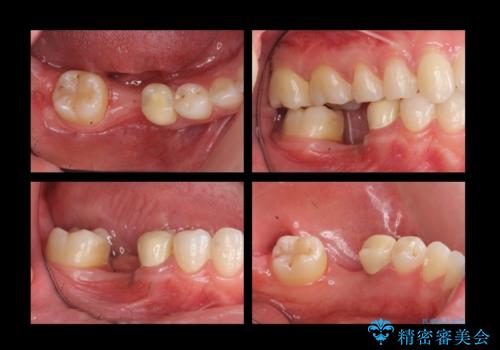

奥歯のインプラント

- 右下6番が保存不可能だったため、やむなく抜歯しました。

インプラント治療をご希望されたため、植立を行いました。

インプラントを入れる際、部分的に骨を増やす処置を行っています。